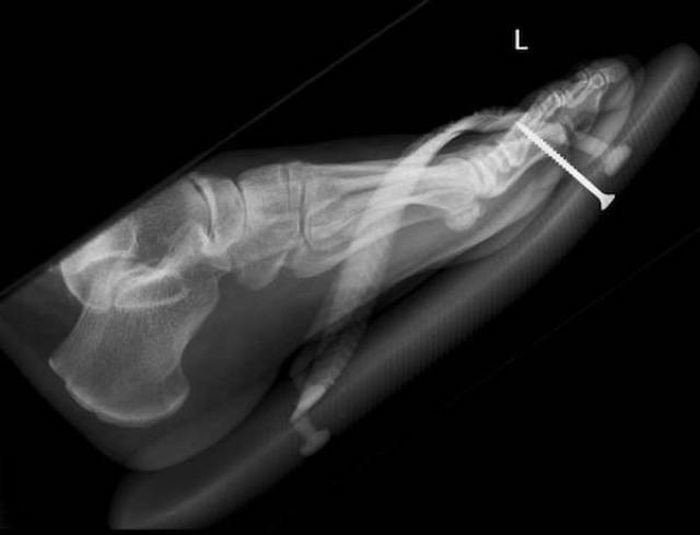

Предметы, которые не очень хочется видеть внутри себя

Под рентгеновскими лучами порой видны не только внутренние органы и кости, но и инородные тела, попавшие в организм

Истории попадания этих предметов в организм могут быть самыми невероятными и запутанными, но больше всего медиков интересует процесс их извлечения, впрочем, в этом заинтересованы и сами пациенты, допустившие нечто подобное со своим телом.